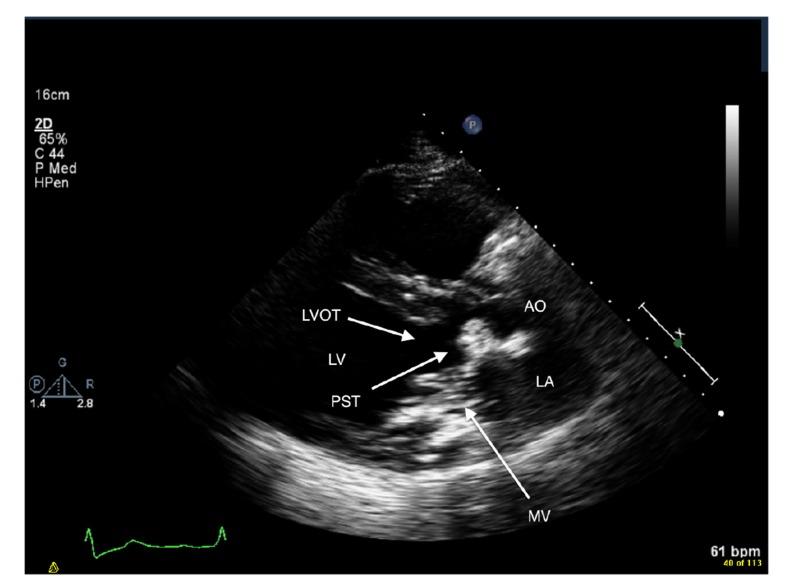

Caseous calcification of the mitral annulus (CCMA) is believed to have a benign prognosis. Several authors have recommended conservative management in asymptomatic patients. However, the prevalence of cerebrovascular events (CVE) in patients with CCMA has never been evaluated before. The aims of this study are to investigate whether patients with CCMA are at increased risk of cerebral embolization, and to determine whether elective surgical resection of CCMA should be considered to prevent a cardioembolic stroke.

From our initial search that yielded 1,502 articles, we identified a total of 130 patients with CCMA reported in 86 publications. Literature review revealed that the prevalence of CVE associated with CCMA is 19.2% (25 of 130) which is significantly higher than the prevalence of CVE reported with mitral annular calcification (MAC), 11.8% (214 of 1818) (range 4.8% to 24.1%) ( = 0.01796) (odds ratio = 1.78; 0.95 confidence interval = 1.1278 - 2.8239). Only four of 25 (16.0%) patients with CCMA who suffered a CVE had history of atrial fibrillation (AF).

Based on our review, it would be reasonable to consider elective surgical resection of CCMA in asymptomatic patients who are good surgical candidates, because patients with CCMA may be at increased risk of embolic strokes, which are unrelated to AF.